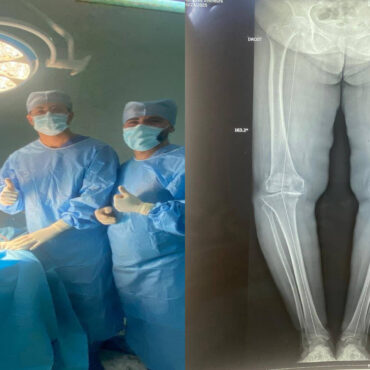

كما تم التأكيد، خلال الجلسة التي اشرف عليها والي قفصة سليم فروجة، على ضرورة تحسين ظروف إقامة الإطار الطبي قصد استقطاب الكفاءات الطبية وضمان استقرارها، حيث تم اقتراح إحداث مقر إقامة مخصص للإطار الطبي داخل المصحة بما يضمن ديمومة الخدمات الصحية، مع السعي لتحديث منظومة التصوير الطبي (المفراس والأشعة)، وإعادة تفعيل آلة التصوير الإشعاعي، والتأكيد على ضرورة التسريع في اقتناء آلة “المفراس” المبرمجة منذ سنة 2024، لرفع جودة التشخيص والخدمات الصحية المسداة بالمصحة.